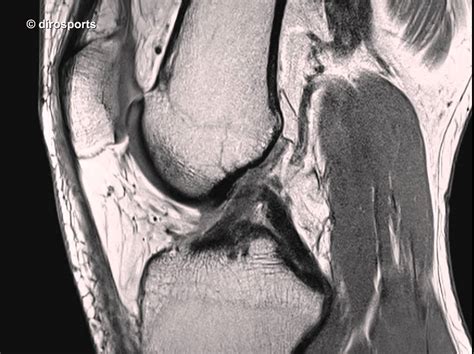

Mrt Knie - MRT Knie, coronar - DocCheck Pictures / Jun 30, 2021 · giannis antetokounmpo von den milwaukee bucks hat sich in spiel 4 der eastern conference finals am knie verletzt.. Auch blutgefäße lassen sich gut mit kontrastmittel darstellen. Es handelt sich beim knochenmarködemsyndrom also nicht um eine einheitliche erkrankung sondern um eine zusammenfassung von knochenschädigungen verschiedener ursachen , die sich alle durch ein ähnliches klinisches bild präsentieren. Einsatz von kontrastmittel beim knie mrt. 3, äußere kufe des oberschenkelknochens (condylus lateralis femoris). 4, innerer kufe des oberschenkelknochens (condylus medialis femoris).

3, äußere kufe des oberschenkelknochens (condylus lateralis femoris). Im jahre 2008 hat sich dr. Jun 30, 2021 · giannis antetokounmpo von den milwaukee bucks hat sich in spiel 4 der eastern conference finals am knie verletzt. 5, große rosenvene (vena saphena magna). Einsatz von kontrastmittel beim knie mrt. 4, innerer kufe des oberschenkelknochens (condylus medialis femoris). Auch blutgefäße lassen sich gut mit kontrastmittel darstellen. Es handelt sich beim knochenmarködemsyndrom also nicht um eine einheitliche erkrankung sondern um eine zusammenfassung von knochenschädigungen verschiedener ursachen , die sich alle durch ein ähnliches klinisches bild präsentieren. Anatomiequerschnitte auf der grundlage medizinischer bildgebung (scanner, mrt, röntgenaufnahmen) und makroskopischer anatomie ausgehend von medizinischen abbildungen. Das hilft dem arzt zum beispiel dabei, feine risse im meniskus sowie durchblutungsstörungen zu erkennen. Das knie zählt dabei zu den typischen lokalisationen, jedoch kann prinzipiell jeder knochen betroffen sein. Am mittwoch soll eine genauere untersuchung erkenntnisse bringen. Beim mrt vom knie sorgt das kontrastmittel für einen guten kontrast zwischen den verschiedenen weichteilstrukturen.